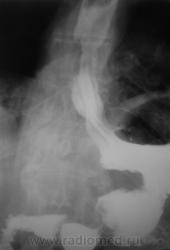

Пациент направлен на рентгенологическое исследование пищевода после ФГДС с диагнозом - "Пищевод Барретта".

Пациент первично был направлен в онкологический диспансер (областной). От туда он был направлен по месту жительства для производства ФГДС, которая и была проведена, был выставлен выше указанный диагноз.

После ФГДС, врач эндоскопист рекомендовал провести рентгеновское исследование пищевода.

1. Пищеводно-желудочный переход отсутствует - это одно из подтверждений пищевода Баррета.

2. Наблюдаемое сужение может быть следствием эзофагеального стеноза в зоне трансформации эпителия - это тоже подтверждение пищевода Баретта, но как без биопсии дифференцировать с инфильтративной формой рака....

3. Нишеподобное выпячивание по левой стенке может быть пептической язвой - это тоже характерно для пищевода Баретта....

4. Изменения в кардиальном отделе желудка по медиальной стенке - интересное и непонятное явление...думаю без биопсии тут никто не разберется, это и отек слизистой, это и рост в просвет...

Вывод, столь серьезная заявка, как пищевод Баретта, тем более с учетом возможности развития на этом фоне опухолевого поражения, требует ОБЯЗАТЕЛЬНОГО гистологического подтверждения....без биопсии НИКУДА....увы...

Циркулярное сужение в н/3 + отсутствие складок на уровне поражения + формирующееся престенотическое расширение = рак н/3 пищевода. Ну, а Барреты? А Барреты потом...